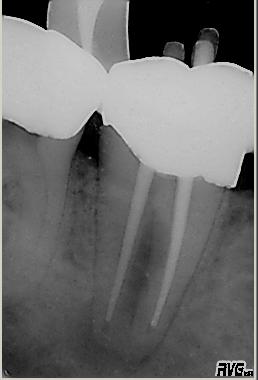

WF Kontrolle

WF Kontrolle im Juli 2003. Dichte dreidimensionale Wurzelfüllung in vertikaler Kondensation erwärmter Guttapercha mit System B und Obtura 2. Die ursprünglich geplante Nachresektion wurde aufgrund des Ergebnisse nicht durchgeführt